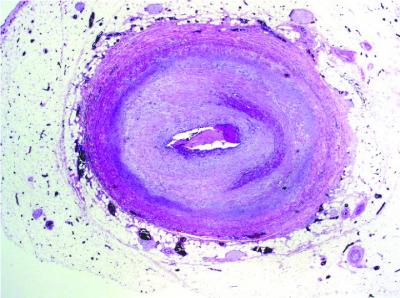

The team focused on the mechanism behind narrowing of the donor's grafted blood vessels, which blocks blood from reaching the transplanted organ. Starved of oxygen and other nutrients, the organ eventually fails, forcing the patient back on the transplant waiting list.

"Chronic rejection is the No. 1 cause of organ failure in the first year of transplant," explained Elaine Reed, director of the UCLA Immunogenetics Center and professor of pathology at the David Geffen School of Medicine at UCLA. "In the first five years, some 40 percent of organs fail after transplant due to blockage of the grafted blood vessels. Currently, we have no way to treat this deadly condition."